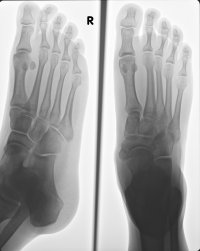

The wound has healed nicely but the pain in my ankle is still plaguing me so I finally decided to get an X-Ray just in case something was actually wrong. The Radiologist says that I haven’t broken anything but that I should “keep off it for a few days to give it a chance to heal”… I assume he’s a big fan of levitation then.